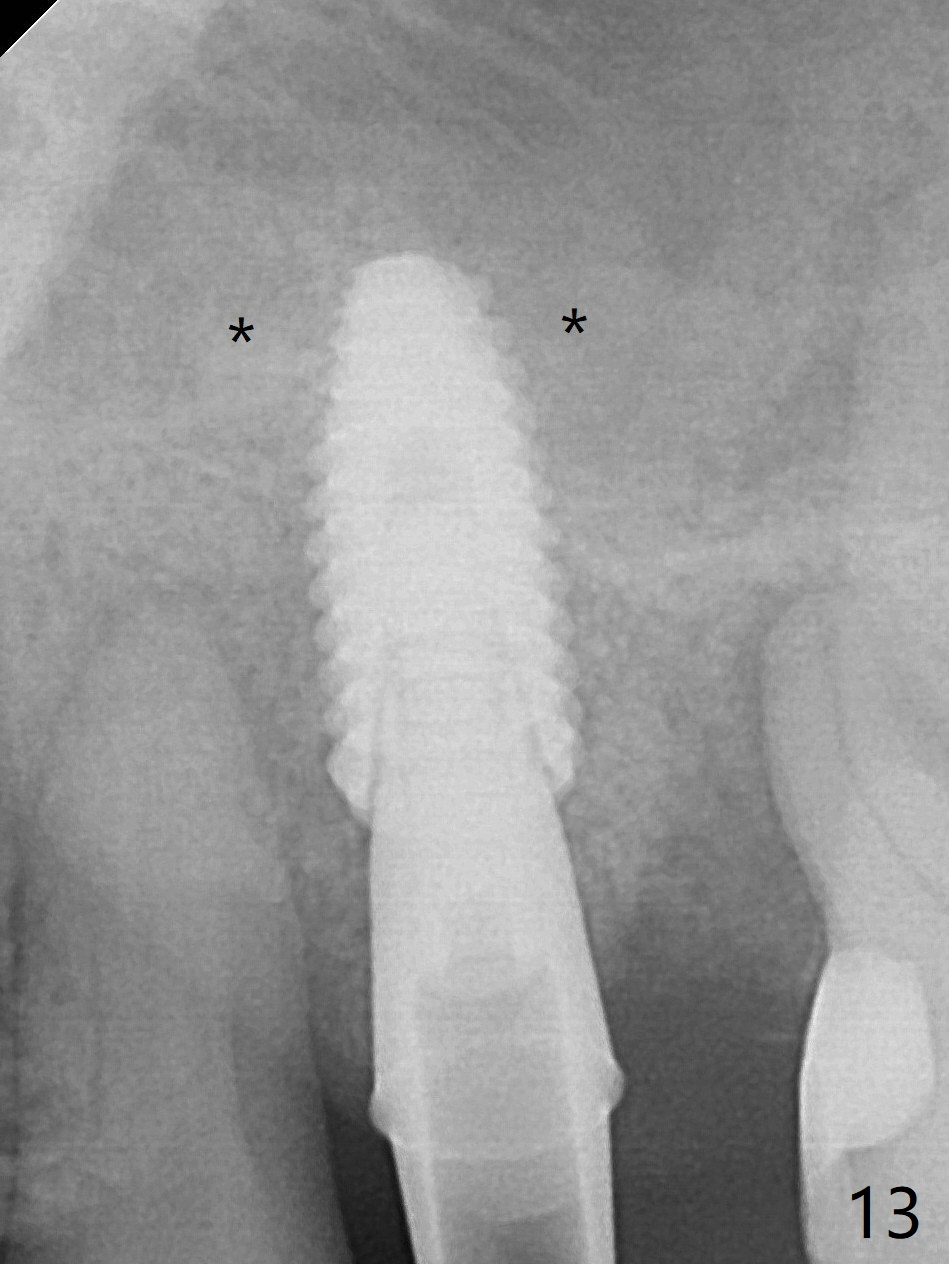

After placing PRF membrane and Vanilla graft for sinus lift (Fig.13 *), a 4.5x10 mm definitive implant is placed with loss of control in the trajectory (Fig.12,13). * in Fig.12: bone graft around the implant. Because of hemorrhage, deep position and block of the bone graft for sinus lift, it is difficult to control the entry of the final implant. The latter obviously slips into the original osteotomy. An angled abutment may be needed to correct the trajectory. Nearly 1 month postop, the 4.5x5.5(5) cementation abutment is loose. When it is removed, the patient feels pain from the implant. A 5.5x6 mm healing abutment is placed instead. The implant osteointegrates with trabecular pattern in the sinus 9 months postop (Fig.20 *). A 4.5x5.5(4) mm cementation abutment is used with mesial trimming before impression. The gingival cuff is healthy.